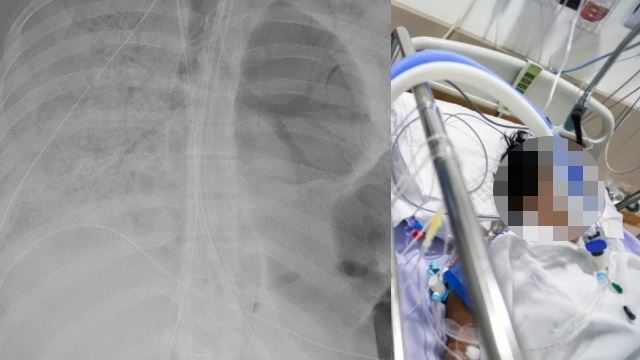

Tambahnya, tiub pernafasan perlu dimasukkan ke saluran trakea dan proses itu hanya boleh dilakukan dalam keadaan pesakit ditidurkan.

Mesin bantuan pernafasan digunakan untuk menjaga pernafasan pesakit dan untuk menambah oksigen ke dalam darah.

Kebiasaannya, hanya pesakit Covid-19 kategori empat atau lima sahaja ditidurkan kerana pesakit memerlukan bantuan pernafasan dan oksigen lebih daripada biasa akibat kegagalan fungsi organ terutamanya paru-paru, jantung dan buah pinggang.